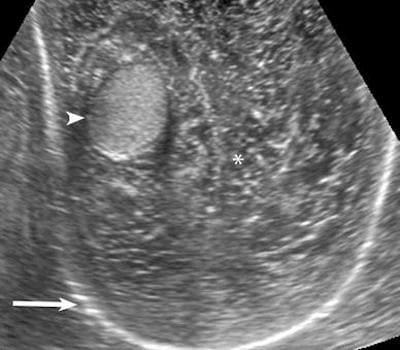

УЗИ яичка в норме . а) Анатомия: 1 . Яичко: • Плотно упакованные извитые семенные канальцы, разделенные тонкими соединительнотканными перегородками: о В яичке взрослого мужчины . . .

Яичко - парный железистый орган эллипсоидной формы, несколько уплощенный с боков . Яичко покрыто фиброзной белочной оболочкой, образующей по задней поверхности . . .

Яичко (testis) — парная мужская половая железа, в которой образуются половые клетки (сперматозоиды) и мужские половые гормоны . Яички имеют овальную форму и плотную . . .